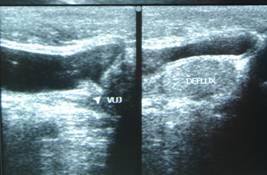

The commonly misleading history given by the parents is that the child may have had a trivial trauma or an insect bite. However, for the clinician the golden rule should be ‘Any acute scrotum is testicular torsion unless proved otherwise’. Investigations like ultrasound and color doppler may be done to help in the diagnosis. However, in the event of any doubt, it is safest to do a surgical exploration of the scrotum. The other uncommon causes of acute scrotum are acute epidydymo orchitis, scrotal abscess, idiopathic scrotal oedema and torsion of appendix of the testis. ●